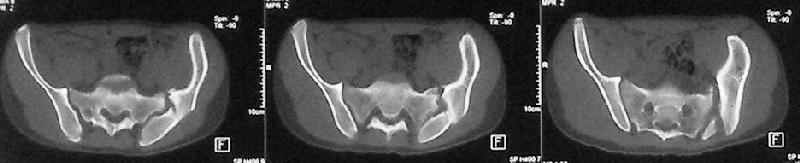

Коллеги, помогите определиться с тактикой лечения пациента. Ув. коллеги, к нам поступил молодой человек 17 лет. Травма в июле 2005- ДТП, т.е. 3 мес назад. Лечился консервативно в "гамаке" 1,5 мес., затем ходьба с костылями без опоры на левую нижнюю конечность, начал на нее опираться 1 нед назад. В настоящее время имеется укорочение порядка 4-5 см, выраженная хромота, передвигается с одним костылем. Кроме того беспокоят боли в пояснично-крестцовой области при ходьбе, неудобство при сидении, невозможность лежать на спине "на жестком", а также на левом боку (субъект худощавый, боль в области крыла) хромота, длительное пребывание на ногах невозможно. На функциональных снимках большой подвижности нет (не привожу из-за плохого качества). Учитывя наличие участков сращений, помогите опредилиться с тактикой. Наш план пока такой: 1. выполнить остеотомии в участках сращений 2.постепенно аппаратом низвести смещенную половину таза. 3.выполнить внутренний остеосинтез передних и задних отделов. Будем признательны за ваш взгляд на тактику леченияэтого больного, а так же на такие проблемы как: места остеотомий, возможные варианты компоновки аппарата, выбор имплантатов для последующего вмешательства.

Уважаемый коллега. Не знаю, прооперировали-ли вы больного или нет, но глядя на Р-граммы захотелось поделится сосбражениями. Укорочение конечности на 4-5 см конечно-же нужно устранить. Вы хотите выполинть остетомию мест сращения, любопытно каким образом? Если пользоваться широкими доступами, то возможно выпонить репозицию открыто и фиксировать погружнными конструкциями как Вы и планируете после репозиции в аппарате. Тем самым устранить укорочение конечности, может быть конечно не оплностью но на 2-3 см то точно. Закрыто же выполнить остеотомию сращений наверное возможно сзади, спереди я бы не рискнул, а лонные кости рубить надо. Что касается лечения аппаратом, то я ученик "вашей школы" что вашим аппаратом можно устранить смещения полностью. Но стоит ли подвергать пациента длительному дискомфорту и повышать риск воспалительных осложнений? Учитывая Ваш опыт лечения таких повреждений таза я бы остановился на одномоментной открытой репозиции и остеосинтезе. С уважением Гринь Алексей.